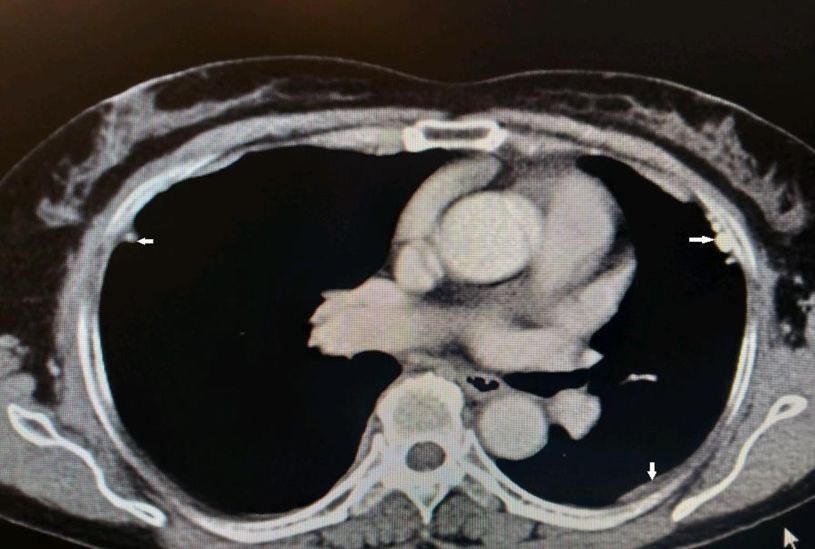

•入院后查血肿瘤标志物正常,T-SPOT阴性。胸部CT见两肺内少许絮索条影,两侧胸膜结节状增厚伴散在钙化。

图示:患者两侧胸膜可见结节、钙化影(白箭)

到目前为止,除了胸腔积液之外,仔细阅读该患者胸部CT发现该患者的另外一个特点就是胸膜增厚、结节、钙化影。通过这一线索,不排除有胸膜来源疾病的可能。